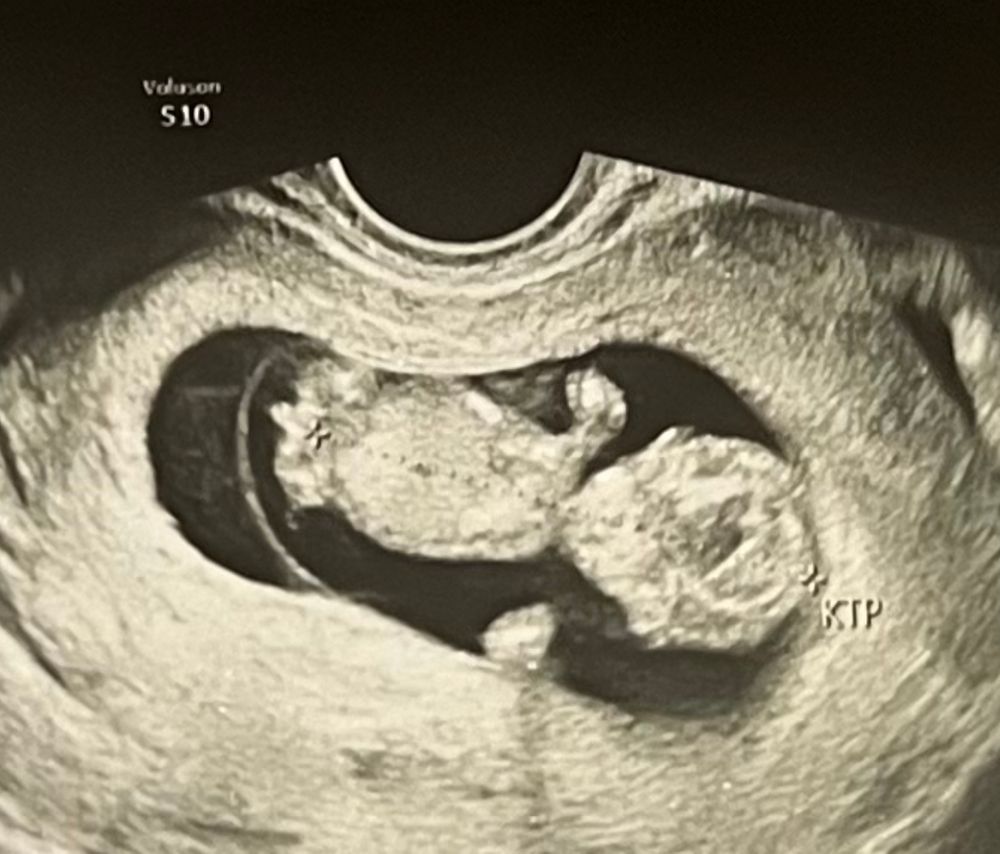

Видно ли пол?)

Срок какой? Если до 14 недель только сагиттальному срезу можно попробовать предположить) ни по фронтальной оси ничего не увидите, там угол наклона полового бугорка к спинке смотрят )

Катерина, 11 недель) ну вот да, наверное так не определить, видно чего-то только непонятно что это)

А вот это вон там не писюлька торчит?🫣

Валентина Новичкова, а писюлька будет торчать до 14 недель хоть у мальчика, хоть у девочки) 🤷‍♀️